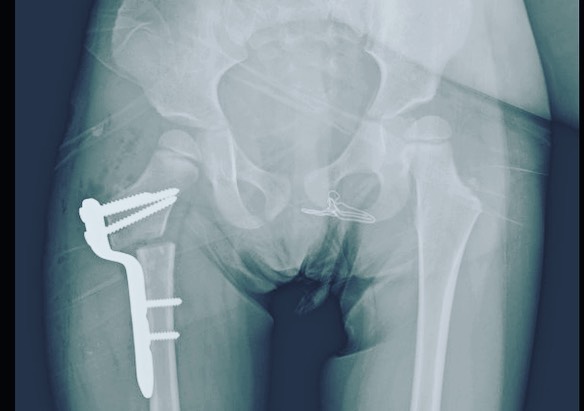

Quiero compartirles que doy de alta a mi pacientita Leilany, de 5 años. La operé por displasia de cadera causada por coxas valgas (región proximal del fémur muy vertical), que alteraba la morfología de su cadera y provocaba disfunción a largo plazo. Le realicé un tratamiento quirúrgico para corregir la deformidad y ahora está al 💯, lista para jugar y hacer travesuras. 🎉